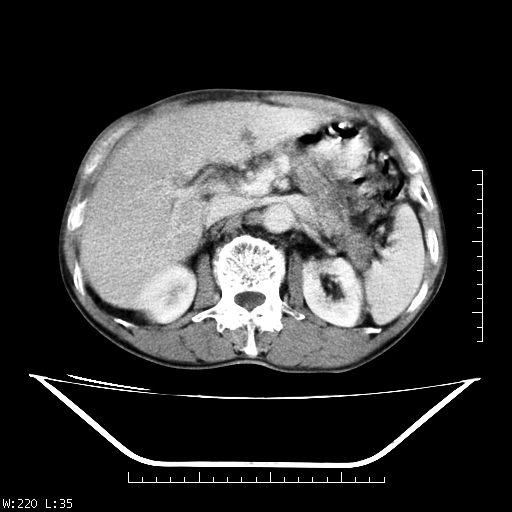

男,70,右上腹痛两月,有乙肝病史,b超提示肝占位,ct如下,请会诊。

补充:该患者afp9.24

肝右叶类圆型密度减低影,密度不均,边界清晰其内可见更低密度影,腹膜后可见小淋巴结肿大,增强扫描动脉期病灶明显强化,静脉期及延时扫描见强化不明显,快进快出表现。

1.肝右叶低密度影考虑为肝癌;

2.肝转移待除外。

平扫呈低密度占位,动脉期斑片状明显强化,病灶边缘清晰,见假包膜;门脉期呈低密度,符合肝癌快进快出强化特征

补充:该患者afp 9.24,似乎与原发性肝癌不符合,另胰头区结构正常吗?请大家继续发表高见。